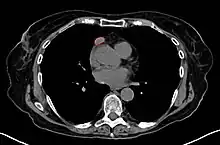

When a thymoma is suspected, a CT/CAT scan is generally performed to estimate the size and extent of the tumor, and the lesion is sampled with a CT-guided needle biopsy. Increased vascular enhancement on CT scans can be indicative of malignancy, as can be pleural deposits.[3] Limited biopsies are associated with a very small risk of pneumomediastinum or mediastinitis and an even-lower risk of damaging the heart or large blood vessels. Sometimes thymoma metastasize for instance to the abdomen.[5]

An encapsulated cystic thymoma.

A locally invasive circumscribed thymoma (mixed lymphocytic and epithelial, mixed polygonal and spindle).